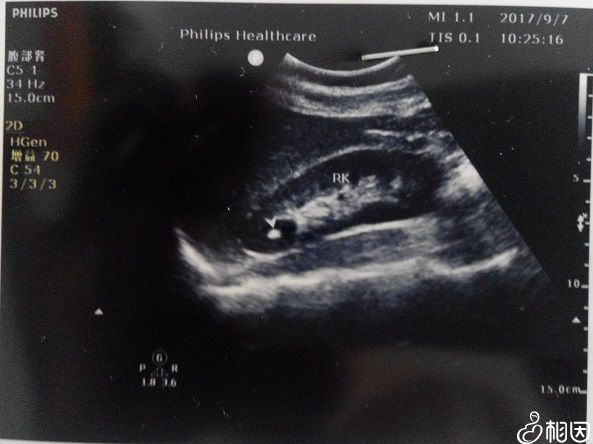

相比于过去的B超检查,四维彩超的优势很明显,其清晰的图像功能使得检查的准确率更高,对于高龄女性来说,四维的排畸功能可以让孕妇尽早确定胎儿情况,并作及时处理,这也是医生建立女性做该项检查的主要原因。

B超是二维图像

二维图像检查的准确率更低